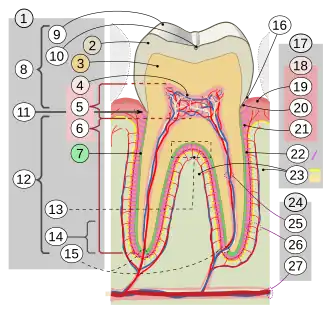

17. Periodontium

:18. Gingiva: ::19. free or interdental ::20. marginal ::21. alveolar :22. Periodontal ligament :23. Alveolar bone 24. Vessels and nerves: :25. dental :26. periodontal :27. alveolar through channel

In dental anatomy, the apical foramen, literally translated "small opening of the apex," is the tooth's natural opening, found at the root's very tip—that is, the root apex — whereby an artery, vein, and nerve enter the tooth and commingle with the tooth's internal soft tissue, called pulp. Additionally, the apical foramen is the point where the pulp meets the periodontal tissues, the connective tissues that surround and support the tooth. The foramen is located 0.5mm to 1.5mm from the apex of the tooth. Each tooth has an apical foramen.[1]